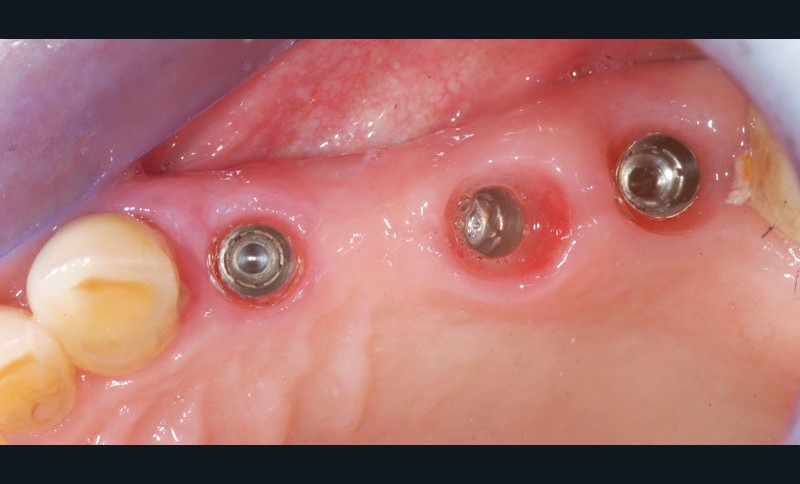

Une fois les transferts pick-up EV® transvissés, le porte-empreinte Tray, fenestré en regard des transferts, est chargé de matériau monophase Impregum™ Penta™ Soft (3M ESPE). Du matériau est déposé autour des transferts à l’aide d’une seringue. Après dévissage des transferts, ces derniers sont emportés dans l’empreinte et les analogues d’implants sont transvissés.